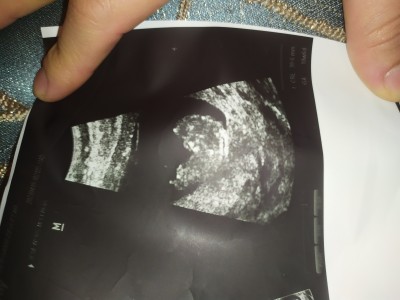

Tamamen eğlencesine soruyorum doktor bugün tahmin yapcak gibi oldu yanılma olur diye söylemedi

Kafa yapısı tam belli olsaydı bir tahmin olurdu birde betan kaçtı ikili test felan yaptırdıysan az çok onlardan anlayıp yorum yapıyorum ve genelde doğru çıkıyor

(4 puan) tarafından

Betaya en son 12 Mart'ta baktırmıştım 145750 civarı birşeydi ikiliye daha gitmedim bir iki haftaya gidicem

(1,661 puan) tarafından

Erkek bebek olabilir o zaman canım kafa yapısında alın kısmı biraz çıkık ise erkek bebek kız bebeğinki daha top daha yuvarlak

Erkek canım pipi ben burdayım diyor☺️